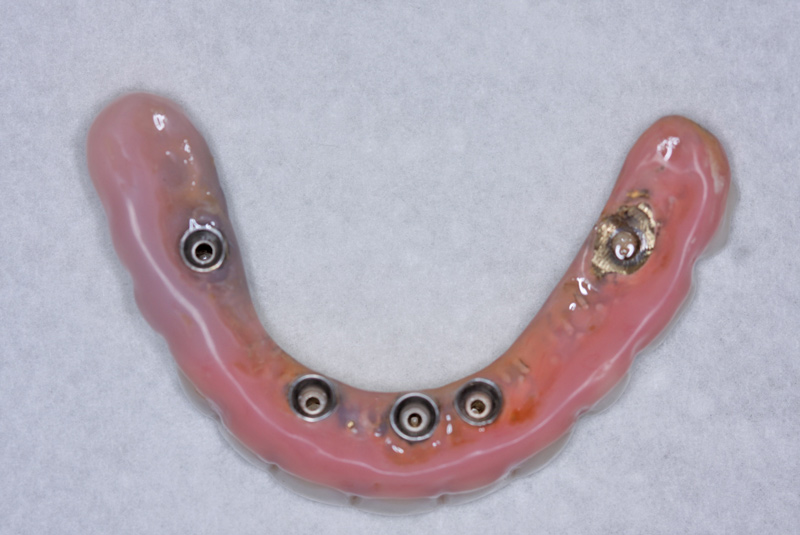

Fig 8. The underside of the prosthesis was then cleaned, adjusted, and polished.

Figure 8

Fig 7. View of the black processing ball before removal.

Figure 7